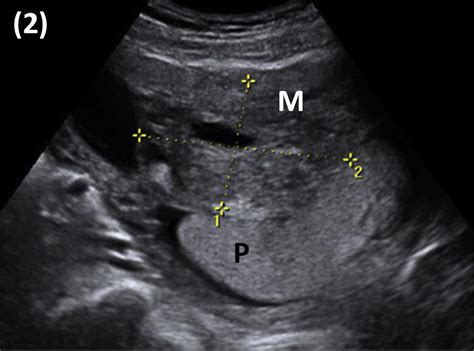

During the early stages of pregnancy, the fertilized egg travels to the uterus and implants itself. The placenta develops wherever that implantation occurs. If it implants on the front wall of the uterus, it is classified as an anterior placenta. Conversely, a posterior placenta attaches to the back wall, and a fundal placenta attaches near the top. An anterior placenta ultrasound typically reveals this position during your mid-pregnancy morphology scan, usually conducted between 18 and 22 weeks.

When you arrive for your scan, the sonographer will use a handheld device called a transducer. By applying a water-based gel to your abdomen and moving the transducer over the surface, the machine transmits sound waves that create images of your baby and the surrounding structures. During this process, the technician will identify the placenta's location to ensure it is not covering the cervix.

You might wonder if an anterior placenta makes a C-section more likely or affects the labor process. The truth is that for the vast majority of cases, it does not. The placenta’s location on the front wall does not generally interfere with the baby’s ability to descend into the birth canal. The primary concern medical teams look for during an anterior placenta ultrasound is placenta previa—a condition where the placenta covers the cervix. If the placenta is located in the anterior position but is far enough away from the cervix, it is perfectly safe for a vaginal delivery.